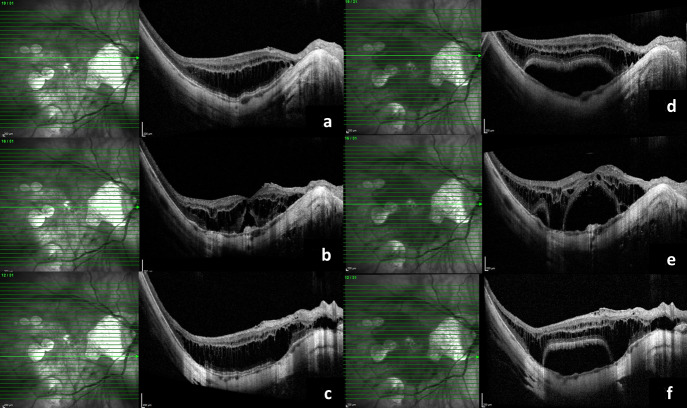

The sequence of events in six years of a myopic traction maculopathy.

Methods: Our female patient who is a high myope developed myopic choroidal neovascular membrane (CNVM), for which she received three anti-vascular endothelial growth factor injections (VEGF). It was scarred for a while. Later she developed myopic foveoschisis with macular detachment which progressed over a period with deterioration of vision.

Results: She underwent pars plana vitrectomy with silicone oil tamponade. Oil removal was done eight months later. At the last follow up visit, her macula was flat with stable vision.